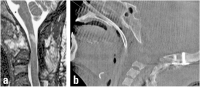

Abbildung 10a-b: (a) Sagittales T2-MRT nach okzipito-zervikaler Stabilisierung und transoraler Densresektion. Im Myelon erkennbare strukturelle Schädigung durch die ursprüngliche Kompression. (b) Intraoperative 3-D-Darstellung des kranio-zervikalen Überganges nach transoraler Densresektion.

Keywords: intraoperative 3-D-DarstellungMRTMyelonokzipito-zervikale Stabilisierungtransorale Densresektion